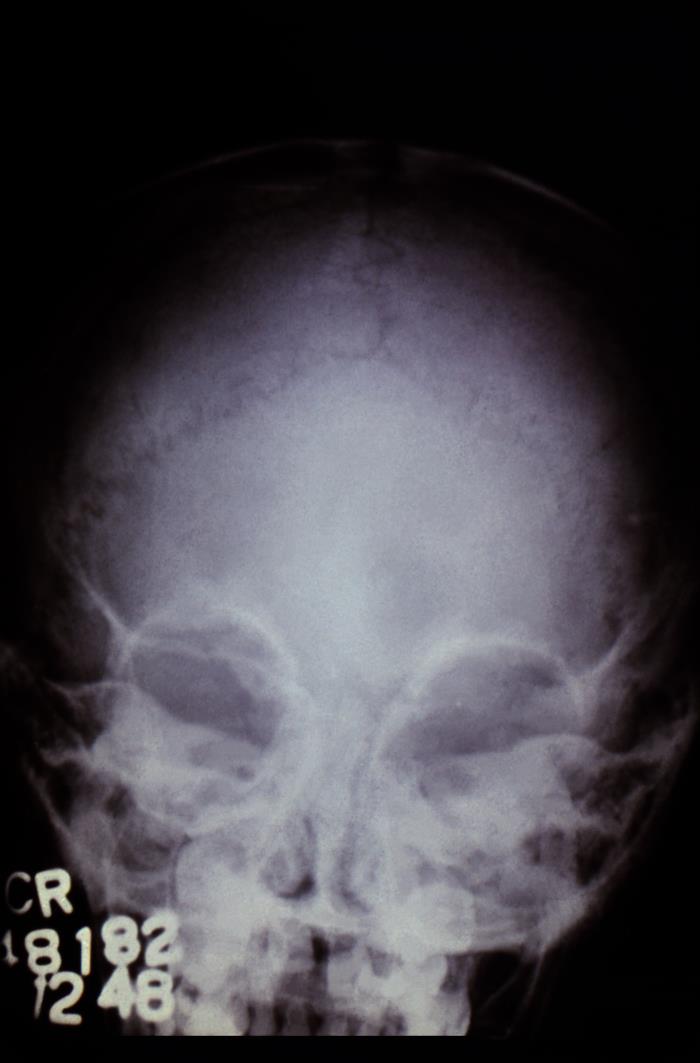

This image of an anterior cranial radiograph highlighted the osseous pathology that had been caused by a case of North American blastomycosis, which had been caused by the fungal organism, Blastomyces dermatitidis.